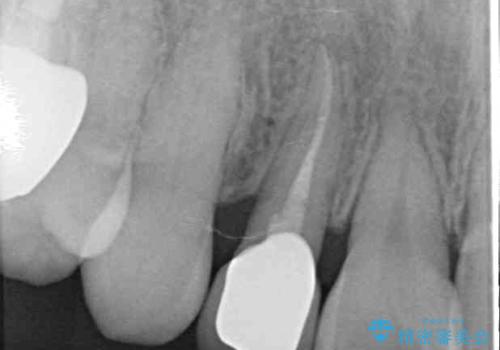

レントゲン写真より、歯根の炎症が認められなかったため、ファイバーコアによる土台築製後、オーダーメイドタイプのオールセラミッククラウンにて補綴することとしました。